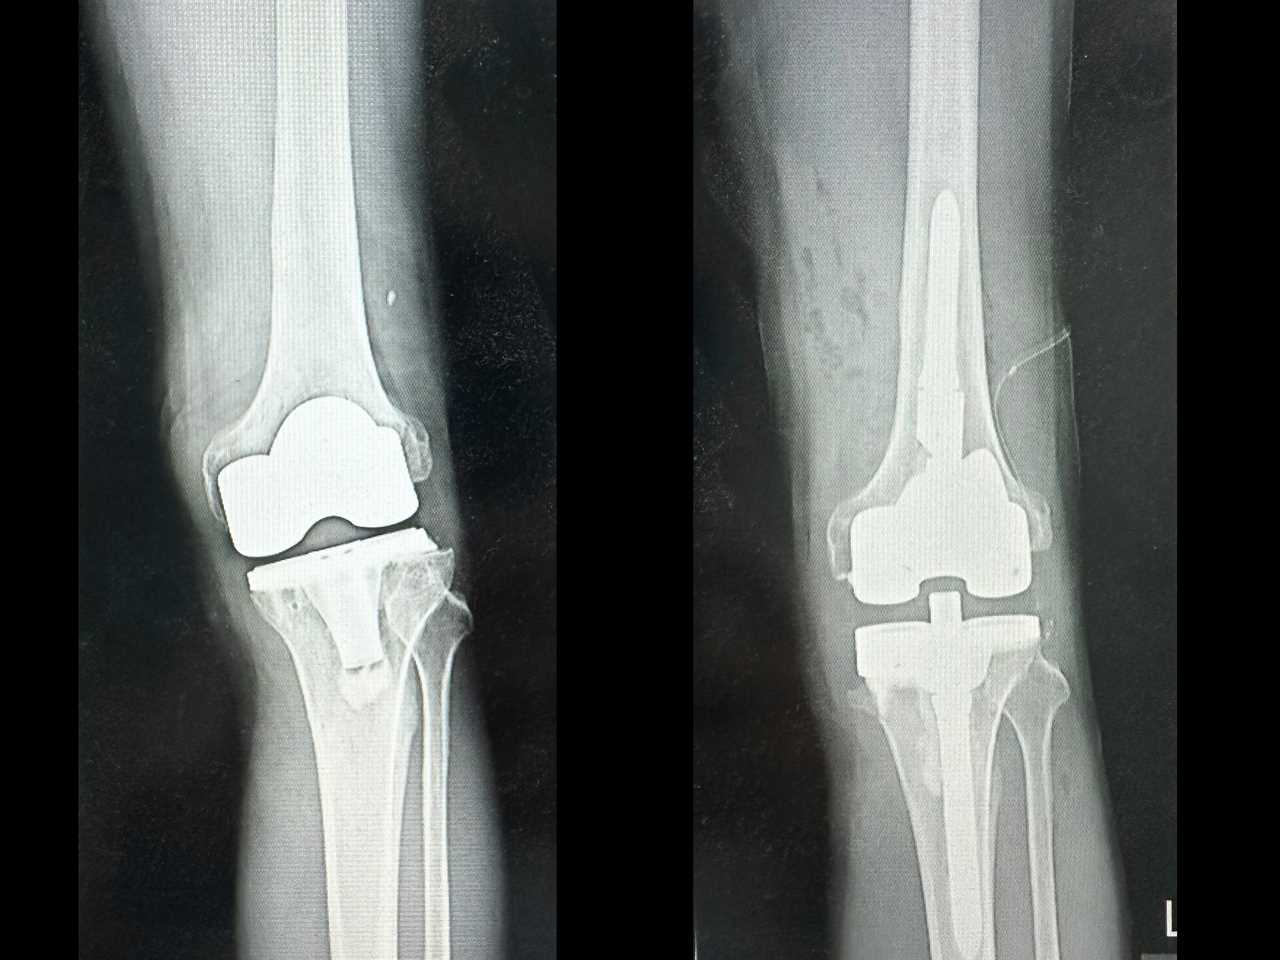

林先生經由親友介紹,轉到台中慈濟醫院趙子鎔醫師門診檢查。X光與電腦斷層顯示,原本置換的人工關節角度出現偏差,導致膝關節軸向錯位、受力不均。趙醫師表示,人工關節應與人體重心軸線垂直,但病人術後角度卻反向歪了約十度,造成走路一踩就歪,膝蓋反覆發炎積水而疼痛。

►人工膝關節翻修再置換前(左)與後(右)X光比較。